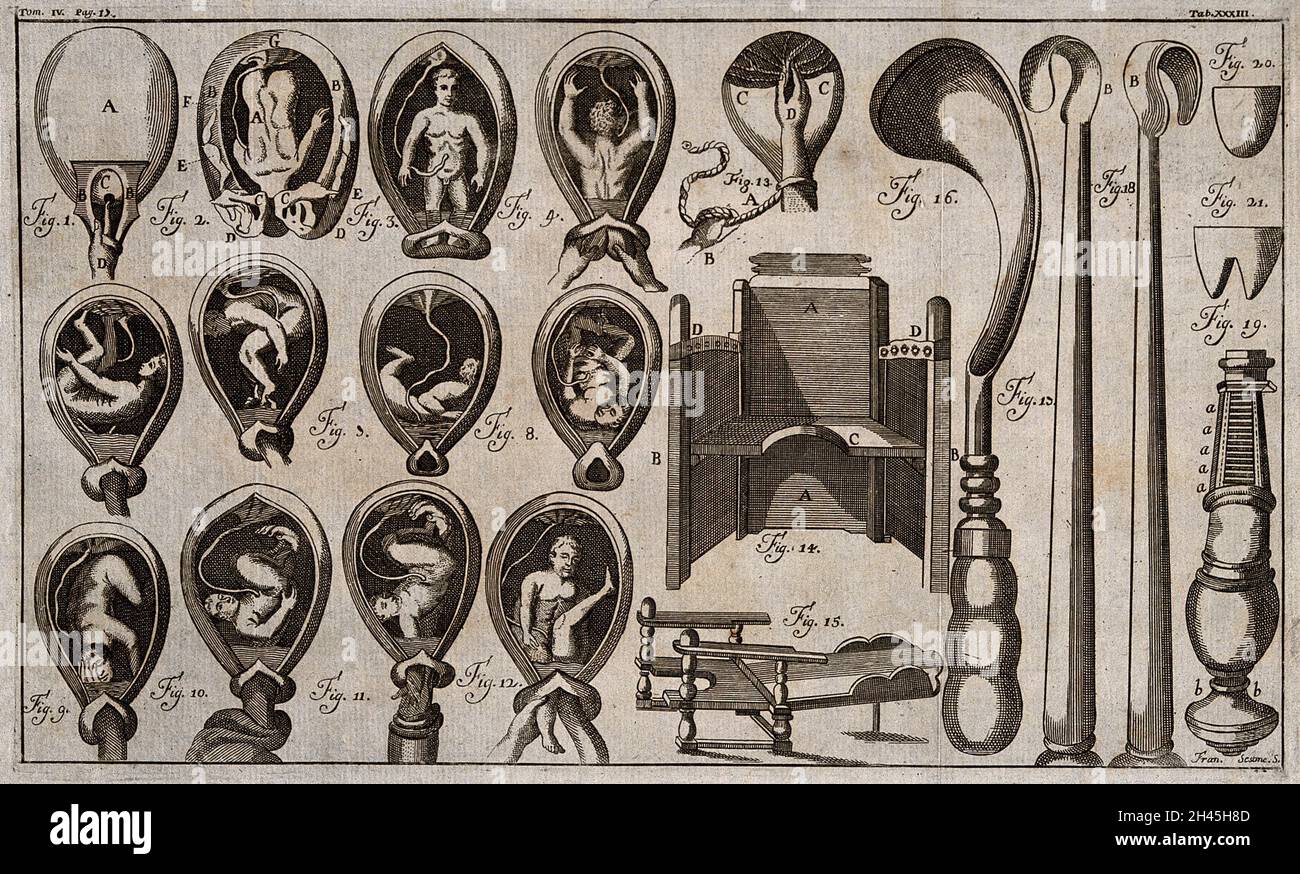

Eight diagrams illustrating babies in the womb in different positions about to enter the world. Etching by Barlow. Stock Photohttps://www.alamy.com/image-license-details/?v=1https://www.alamy.com/eight-diagrams-illustrating-babies-in-the-womb-in-different-positions-about-to-enter-the-world-etching-by-barlow-image449997775.html

Eight diagrams illustrating babies in the womb in different positions about to enter the world. Etching by Barlow. Stock Photohttps://www.alamy.com/image-license-details/?v=1https://www.alamy.com/eight-diagrams-illustrating-babies-in-the-womb-in-different-positions-about-to-enter-the-world-etching-by-barlow-image449997775.htmlRM2H434N3–Eight diagrams illustrating babies in the womb in different positions about to enter the world. Etching by Barlow.

A system of obstetrical tables, with explanations... Stock Photohttps://www.alamy.com/image-license-details/?v=1https://www.alamy.com/a-system-of-obstetrical-tables-with-explanations-image450080710.html

A system of obstetrical tables, with explanations... Stock Photohttps://www.alamy.com/image-license-details/?v=1https://www.alamy.com/a-system-of-obstetrical-tables-with-explanations-image450080710.htmlRM2H46XF2–A system of obstetrical tables, with explanations...